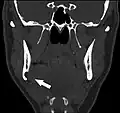

Coronal computed tomograph of the same person (Stafne defect arrowed).